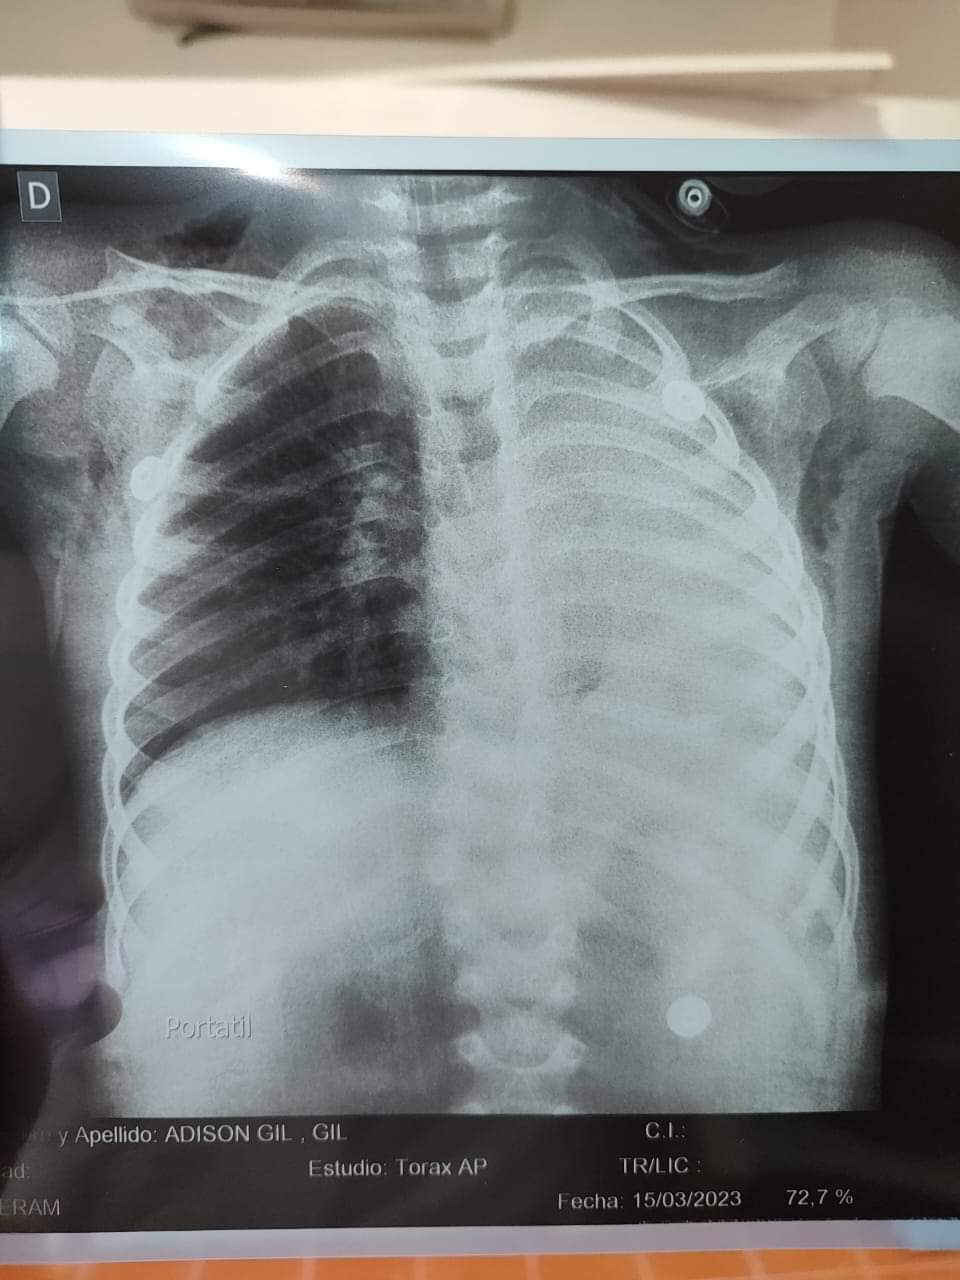

Morínigo indicó que la radiografía a la que fue sometida el niño mostró que el pulmón izquierdo estaba totalmente cerrado. “Los médicos intervinientes se llevaron una gran sorpresa al encontrar que un grano de maíz obstruía su vía respiratoria. Se montó todo el equipo en terapia y llevaron a cabo la broncoscopia”, acotó.